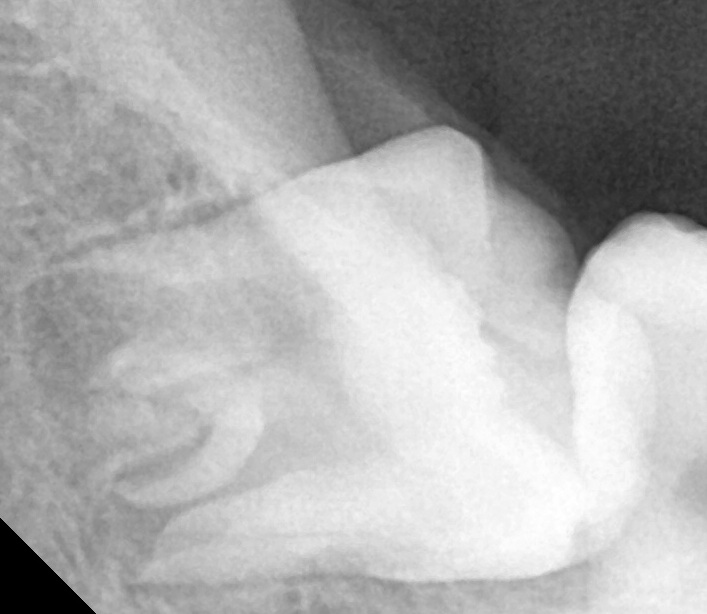

반대쪽과 다르게 누워서 자라고 있는 거 보이시죠??

지금도 잇몸에 불편감을 주는데

앞으로도 계속 염증을 일으킬 케이스!

완전히 누워있기에 저작기능은 전혀 못하는 상황에

오히려 옆 치아에 충치를 일으킬 가능성이

현저해보여 최대한 빨리 뽑는 방향을 말씀드렸습니다.